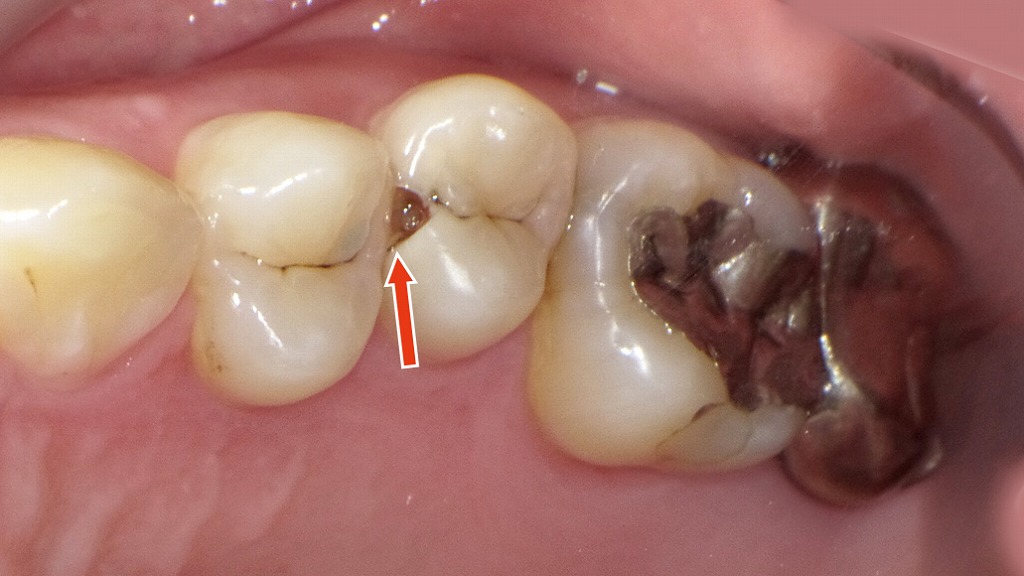

この写真は右上の小臼歯から大臼歯にかけての口腔内写真です。矢印の指している部分(上顎右側第2小臼歯=5番の近心面)に、以下のような特徴が見られます。

🦷 観察所見

- 5番近心面に虫歯(う蝕)の穴

矢印部分に黒褐色の窪みがあり、隣接面う蝕(コンタクトカリエス)が確認できます。初期ではなく、象牙質まで進行している可能性が高い状態です。 - 食べ物が詰まりやすい隙間

4番(第1小臼歯)との接触点が緩く、食片圧入が起きやすい状況。患者は「食べ物が詰まる」「歯ぐきが痛い」などの症状を訴えています。 - コンタクト(歯と歯の接触点)のずれ

本来であれば、4番と5番の間にしっかりと接触点が形成されている必要がありますが、歯並びの乱れからわずかにずれています。これが食片圧入や虫歯の原因になっています。 - 辺縁隆線(咬合面の高さ)のずれ

4番と5番の辺縁隆線の高さに段差があり、歯列全体の咬合バランスにも影響を与える可能性があります。

💡 臨床的考察

このようなケースでは、

- う蝕の除去

- 接触点の適正化(コンタクト形成)

- 咬合面の隆線の高さを整える修復

が必要になります。

また、再発防止のためには、隣接面清掃(デンタルフロスや歯間ブラシ)の習慣化が重要です。

👉 食べ物がよく詰まるのは「ただの不便」ではなく、虫歯や治療後の異常のサインかもしれません。早めに歯科医院でチェックを受けることが大切です。